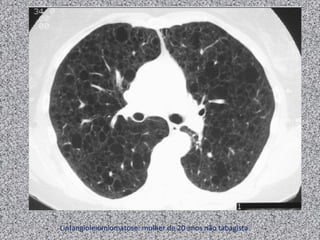

Bronquite crônica

Mulher de 20 anos, não tabagista com dispneia progressiva.

Linfangioleiomiomatose: mulher de 20 anos não tabagista.